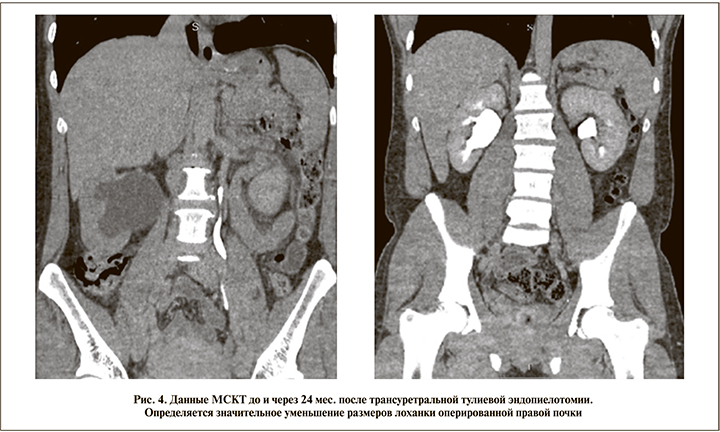

Всем больным на предоперационном этапе провели клинико-лабораторное обследование, включившее сбор анамнеза, жалоб, анализов крови и мочи, ультразвуковое исследование (УЗИ) с допплерографией (оценивали степень пиелоэктазии, камни, наличие добавочного сосуда), МСКТ-урографию или экскреторную урографию (определялась протяженность стриктуры, камни, добавочный сосуд), радиоизотопное исследование функции почек и антеградную пиелографию (для уточнения стояния нефростомического дренажа или сомнений в локализации уровня обструкции). Основное интраоперационное диагностическое мероприятие заключалось в проведении ретроградной уретеропиелографии и уретеропиелоскопии (табл. 1, 2).

Техника трансуретральной тулиевой эндопиелотомии. Под спинномозговой или эпидуральной анастезией пациента укладывали в типичное для трансуретральных вмешательств литотомическое положение. В качестве первого этапа проводили диагностическую трансуретральную уретеропиелоскопию ригидным эндоскопом (наружный диаметр – 7,5–9 Fr, диаметр инструментального канала – 3,5–5 Fr) и выполняли ретроградную уретеропиелографию (рис. 1). Заведение ригидного уретеропиелоскопа в мочеточник в большинстве случаев не требует дилатации мочеточникового устья, позволяет осматривать сужение на глазах и максимально атравматично проводить струну-проводник выше сужения. После осмотра стриктуры и проведения через нее струны-проводника уретеропиелоскоп удаляли и вновь заводили его в мочеточник до сужения помимо проводника. Рассечение стриктуры проводили в латеральном или заднелатеральном направлении лазерным аппликатором диаметром 400–600 мкм, который подводили к сужению по рабочему каналу уретеропиелоскопа. Селективно рассекали все слои и рубцовые ткани суженного участка по всей длине с заходом на визуально неизмененную ткань (рис. 2а, б). Обычно использовали энергию импульса 1 Дж и частоту 10 Гц. К ряду пациентов применяли лазерное волокно 200 мкм, в этом случае оно находилось в одном рабочем канале со страховым проводником. С учетом отличного гемостатического эффекта тулиевого волоконного лазера, обеспечивающего качественную эндоскопическую картину, у ряда пациентов при непосредственном рассечении стриктуры страховой проводник, когда он мешал выполнять инцизию, убирали из операционного поля, подтягивая его в дистальном направлении.